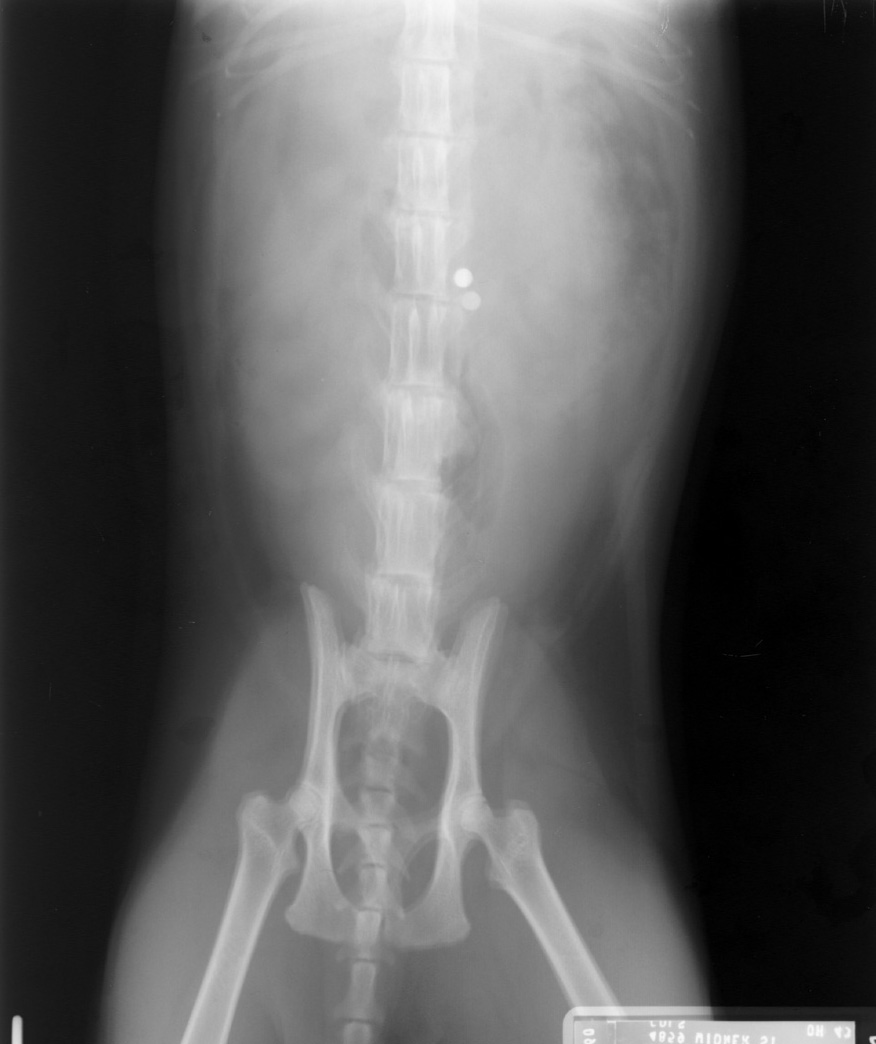

Double Exposures